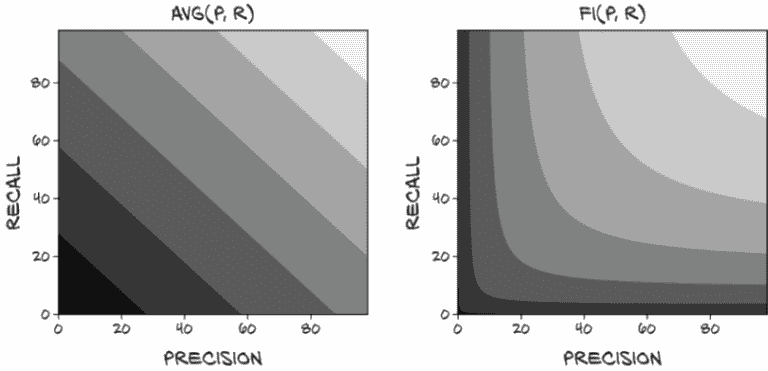

尽管有用,但精确度和召回率都无法完全捕捉我们评估模型所需的内容。正如我们在 Roxie 和 Preston 中看到的,通过操纵我们的分类阈值,可能会单独操纵其中一个,导致模型在其中一个上得分良好,但以牺牲任何实际效用为代价。我们需要一种以防止这种操纵的方式结合这两个值的东西。正如我们在图 12.10 中看到的,现在是引入我们的终极指标的时候了。

乍一看,这可能比我们需要的更复杂,当在精确度和召回率之间进行权衡时,F1 分数的行为可能不会立即显而易见。然而,这个公式有很多好的性质,并且与我们可能考虑的几种其他更简单的替代方案相比较有利。

图 12.10 本章的主题集,重点是最终的 F1 分数指标

一个立即可能的评分函数是将精确度和召回率的值平均起来。不幸的是,这使得avg(p=1.0, r=0.0)和avg(p=0.5, r=0.5)都得到相同的 0.5 分数,正如我们之前讨论的,精确度或召回率为零的分类器通常是无用的。将无用的东西与有用的东西赋予相同的非零分数,立即使平均成为一个没有意义的指标。

然而,让我们在图 12.11 中直观比较平均和 F1。有几件事引人注目。首先,我们可以看到平均值的等高线中没有曲线或拐点。这就是让我们的精确度或召回率偏向一侧的原因!永远不会出现这样的情况,即通过使召回率达到 100%(Roxie 方法)然后消除任何容易消除的假阳性来最大化分数是没有意义的。这就为添加分数至少为 0.5 设置了一个底线!拥有一个质量指标,可以轻松获得至少 50% 的分数,感觉不对劲。

图 12.11 使用avg(p, r)计算最终分数。较浅的值接近 1.0。

注意 我们实际上在这里做的是取精确度和召回率的算术平均值(en.wikipedia.org/wiki/Arithmetic_mean),这两者都是比率而不是可计数的标量值。取比率的算术平均值通常不会给出有意义的结果。F1 分数是两个比率的调和平均值(en.wikipedia.org/wiki/Harmonic_mean)的另一个名称,这是结合这些值的更合适的方式。

与 F1 分数相比:当召回率高而精确度低时,为了将分数移动到平衡的甜蜜点,牺牲很多召回率以换取一点精确度将使分数更接近。有一个漂亮、深刻的拐点,很容易滑入其中。鼓励具有平衡精确度和召回率是我们希望从我们的评分指标中得到的。

假设我们仍然希望有一个更简单的指标,但不会奖励任何偏斜。为了纠正加法的弱点,我们可能会取精确度和召回率的最小值(图 12.12)。

图 12.12 使用min(p, r)计算最终分数

这很好,因为如果任一值为 0,分数也为 0,而要获得 1.0 的分数的唯一方法是两个值都为 1.0。然而,它仍然有待改进,因为使召回率从 0.7 提高到 0.9 而将精确度保持在 0.5 不会改善分数,降低召回率到 0.6 也不会改善分数!尽管这个指标肯定惩罚了精确度和召回率之间的不平衡,但它并没有捕捉到关于这两个值的许多细微差别。正如我们所见,通过简单地移动分类阈值,很容易将一个值换成另一个值。我们希望我们的指标能反映这些交易。

为了更好地实现我们的目标,我们将不得不接受至少更复杂一点。我们可以将这两个值相乘,如图 12.13 所示。这种方法保持了一个很好的特性,即如果任一值为 0,分数也为 0,而分数为 1.0 意味着两个输入都完美。它还有利于在低值处精确度和召回率之间的平衡折衷,尽管当接近完美结果时,它变得更加线性。这并不好,因为我们真的需要将两者都提高才能在那一点上有意义的改进。

图 12.13 使用mult(p, r)计算最终分数

注意 在这里我们正在取两个比率的几何平均值(en.wikipedia.org/wiki/Geometric_mean),这也不会产生有意义的结果。

还有一个问题,几乎整个象限从(0, 0)到(0.5, 0.5)都非常接近于零。正如我们将看到的,拥有一个对该区域的变化敏感的指标是重要的,特别是在我们模型设计的早期阶段。

虽然将乘法作为我们的评分函数是可行的(它没有任何立即淘汰的资格,就像之前的评分函数一样),但我们将使用 F1 分数来评估我们的分类模型的性能。